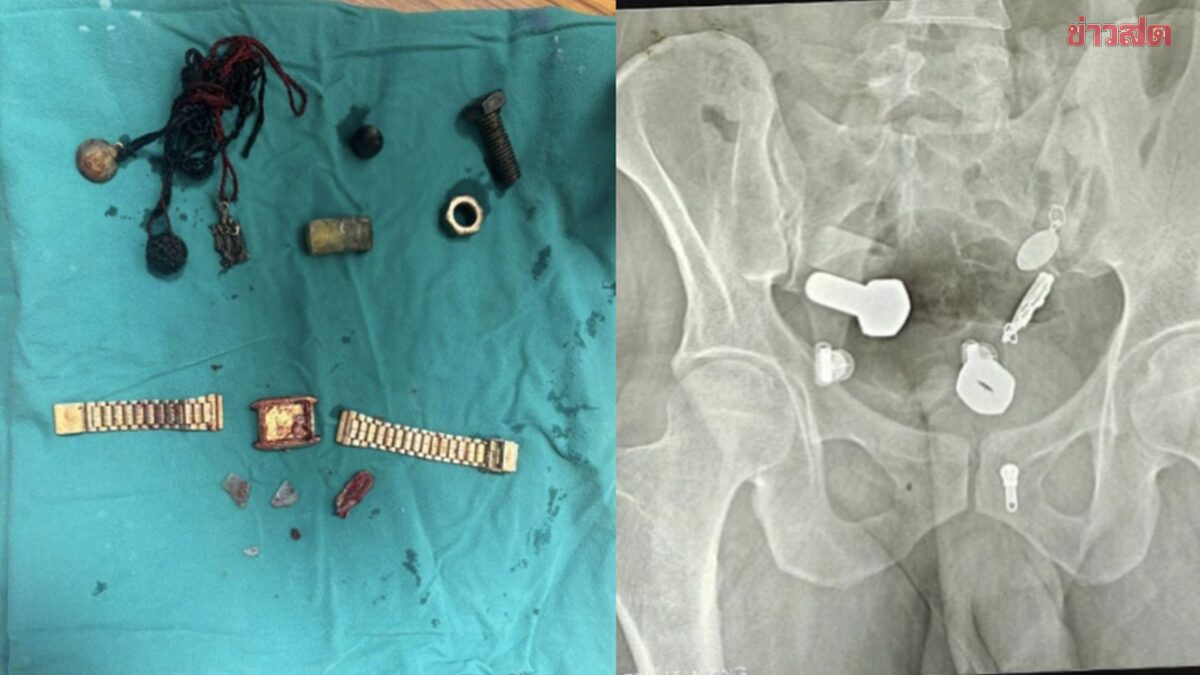

แพทย์ที่ทำการตรวจพบความผิดปกติจากผลเอกซเรย์ ซึ่งแสดงให้เห็นว่า มีนาฬิกาข้อมือติดอยู่ในหลอดอาหาร ขณะที่ในลำไส้ใหญ่พบเศษเหล็กและชิ้นส่วนโลหะต่าง ๆ เช่น น็อต สลักเกลียว และสกรู อัดแน่นสะสมอยู่เต็มไปหมด

แพทย์พยายามใช้วิธีส่องกล้อง (Endoscopy) เพื่อนำวัตถุออก แต่ไม่สามารถทำได้ จึงต้องทำการผ่าตัดใหญ่ที่ใช้เวลานานกว่า 3 ชั่วโมงเพื่อเอาวัตถุทั้งหมดออกจากร่างกาย

รายงานระบุว่า ทีมแพทย์ได้เปิดแผลขนาดเล็กที่ช่องท้องของผู้ป่วย ก่อนค่อย ๆ ดึงวัตถุต่าง ๆ ออกมา ซึ่งรวมถึงนาฬิกาข้อมือเรือนหนึ่ง โดยมีการบันทึกวิดีโอช่วงเวลาที่ศัลยแพทย์นำวัตถุออกมาได้ โชคดีที่หลังจากการผ่าตัดผ่านไป เขาอยู่ในอาการปลอดภัยและกำลังฟื้นตัวได้ดี แม้เหตุการณ์ครั้งนี้จะสร้างความตกตะลึงให้แก่ทีมแพทย์เป็นอย่างมาก